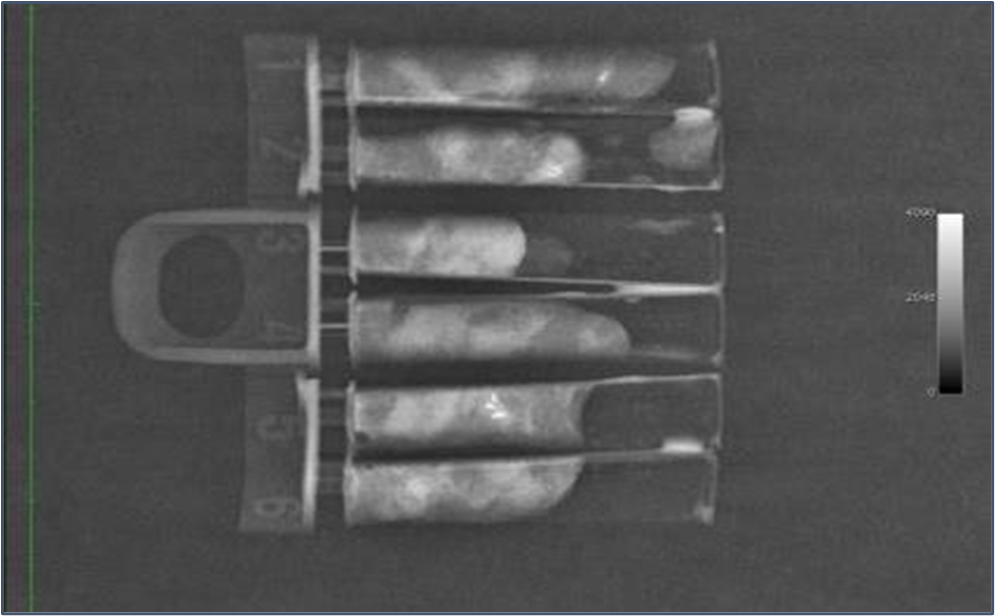

5. 採取した組織(マンモグラフィ装置で撮影)